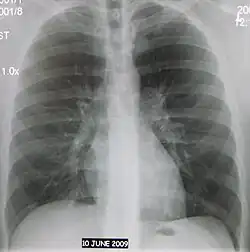

Цифровая флюорограмма

Флюорография даёт уменьшенное изображение объекта. Выделяют мелкокадровую (например, 24×24 мм или 35×35 мм) и крупнокадровую (в частности, 70×70 мм или 100×100 мм) методики. Последняя по диагностическим возможностям приближается к рентгенографии. Флюорография применяется главным образом для исследования органов грудной клетки, молочных желёз, костной системы[1].

Наиболее распространённым диагностическим методом, использующим принцип флюорографии, является флюорография органов грудной клетки, которая применяется прежде всего для выявления туберкулёза и новообразований лёгких. Разработаны как стационарные, так и мобильные флюорографические аппараты[1].